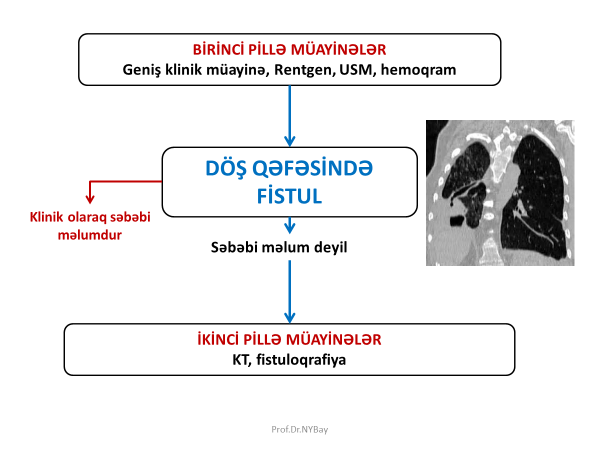

Döş divarında yara və fistul

Döş qəfəsi divarında fistul olarsa əksər hallarda anamnez və klinik müayinə ilə səbəbi məlum olur, məlum olmayan hallarda isə KT və fistuloqrafiya ilə dəqiqləşdirmək mümkündür (Şəkil 5). Döş qəfəsi divarında bronxial, xroniki empiema fonunda meydana gələn plevro-kutanoz və qida borusu fistulları daha çox rast gəlir.

Şəkil 5. Döş qəfəsi divarında yara-fistul